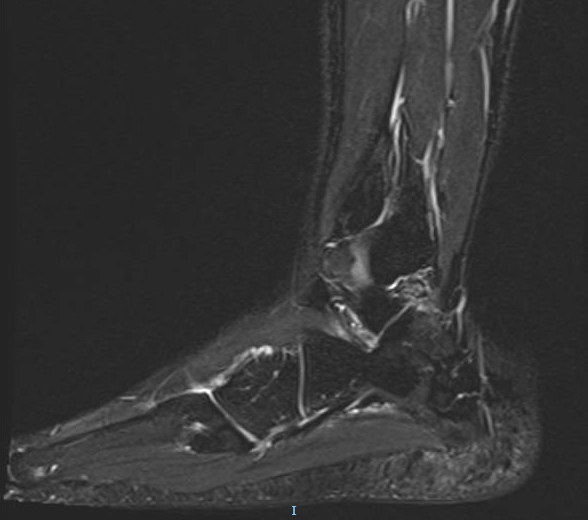

from ultraraastaja.webnode.fi

Os tibiale externum rasitusosteopatia Ultraraastaja